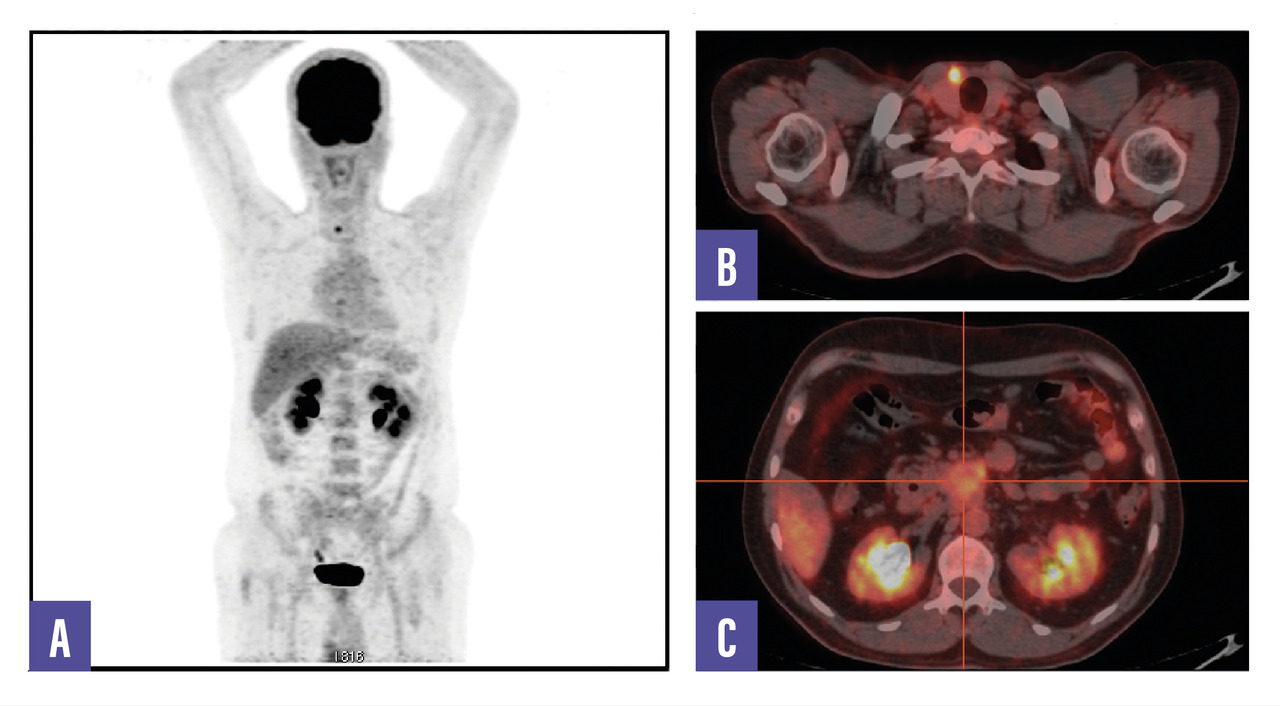

Un homme de 53 ans, sans antécédents, consulte pour des douleurs abdominales diffuses évoluant depuis plusieurs semaines. Le bilan biologique est normal. Une tomodensitométrie abdomino-pelvienne met en évidence une masse rétropéritonéale infiltrante associée à une adénopathie lombo-aortique. La tomographie par émission de positons (TEP-TDM au 18F-FDG) montre un hypermétabolisme léger de la lésion rétropéritonéale, mais l’adénopathie ne fixe pas le FDG (fig. 1). Un foyer hypermétabolique thyroïdien droit est également détecté. Une biopsie échoguidée confirme une tumeur neuro-endocrine digestive bien différenciée de grade 2 (Ki- 67 à 12 %). La scintigraphie au 99mTc-Tektrotyd révèle une fixation intense de l’adénopathie, compatible avec une pathologie neuro-endocrine exprimant les récepteurs de la somatostatine (fig. 2). Un nodule thyroïdien droit conduit à une thyroïdectomie totale, confirmant un microcarcinome papillaire.

L’association entre FRP et tumeur neuro-­endocrine (TNE) est exceptionnelle. Ce cas illustre une TNE bien différenciée, faiblement avide pour le FDG mais fixant intensément le 99mTc-Tektrotyd, combinée à un microcarcinome papillaire thyroïdien.

Ce cas souligne l’importance de l’imagerie métabolique et d’une approche intégrée pour le diagnostic et la prise en charge de pathologies complexes.2